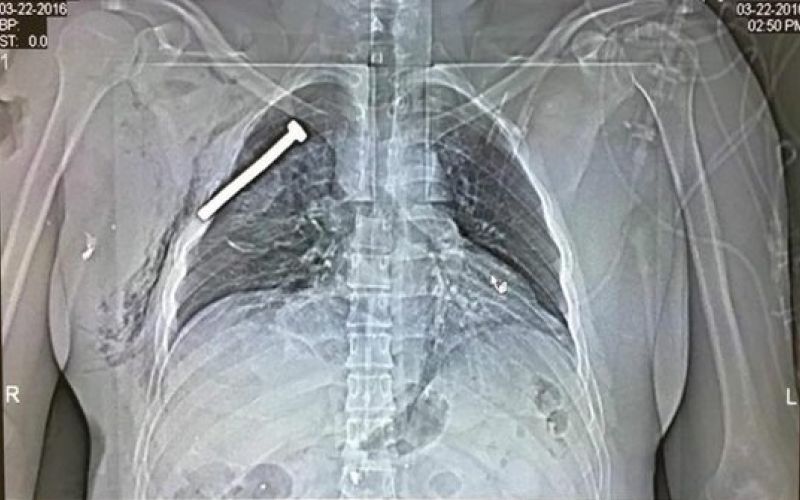

Eni izmed žrtev bruseljskega napada se je vijak ustavil blizu srca

Da bi napadalci z bombami prizadeli in poškodovali kar se da veliko število ljudi, so med eksplozivna telesa vstavili tudi vijake in žeblje.